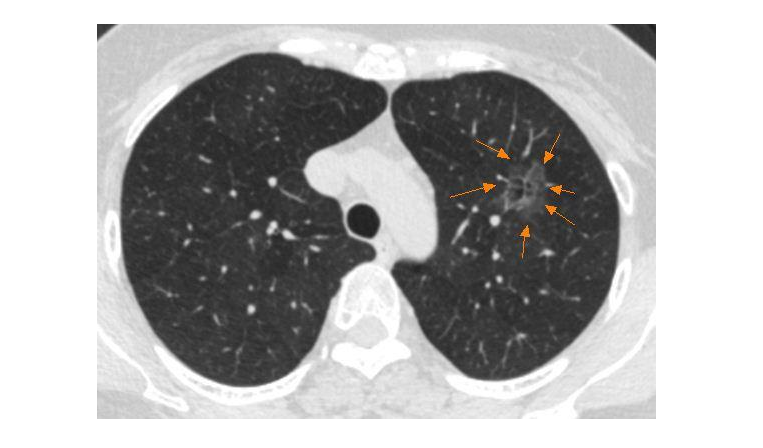

肺磨玻璃结节是肺癌吗?